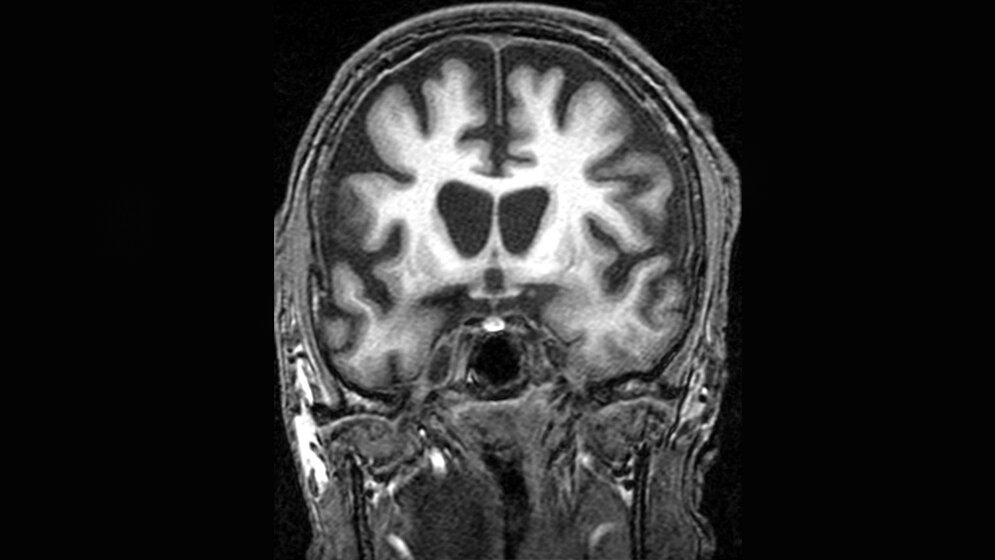

Anhand dieser Daten wollen die Mediziner auch Veränderungen untersuchen, die sie bislang nicht eindeutig interpretieren konnten, beispielsweise eine unerwartete Veränderung der Hirnventrikel, die sie in der aktuellen Studie bei den Patienten beobachteten.